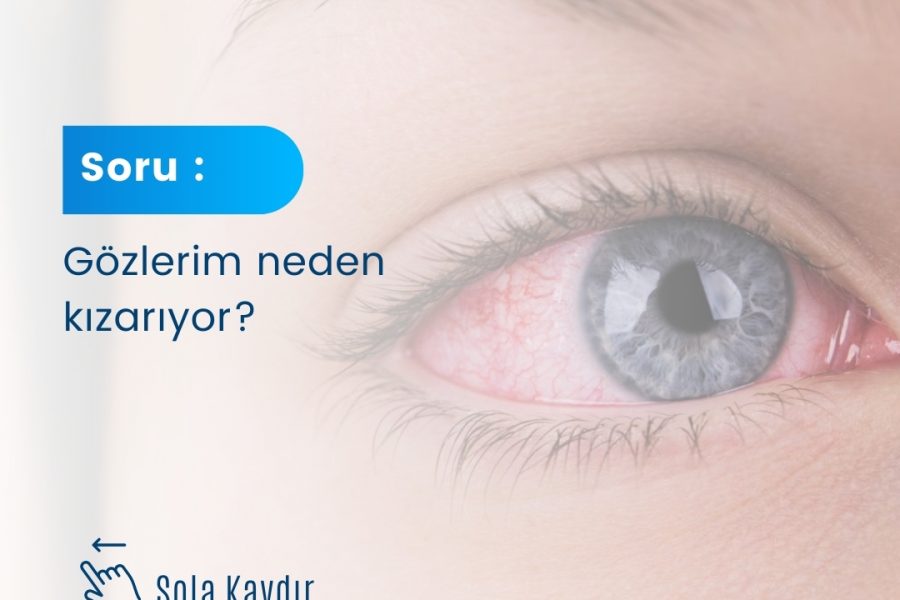

Göz kızarması sık karşılaşılan bir durumdur ve birçok sebebi olabilir. Alerji, göz kuruluğu, göz tansiyonu, göz içinde oluşan iltihaplanmalar, kirpik iltihapları ve arpacık gibi rahatsızlıklar göz kızarmasına neden olabileceği gibi uzun süre bir objeye odaklanmak, yüksek basınç ile öksürmek,... Continue reading